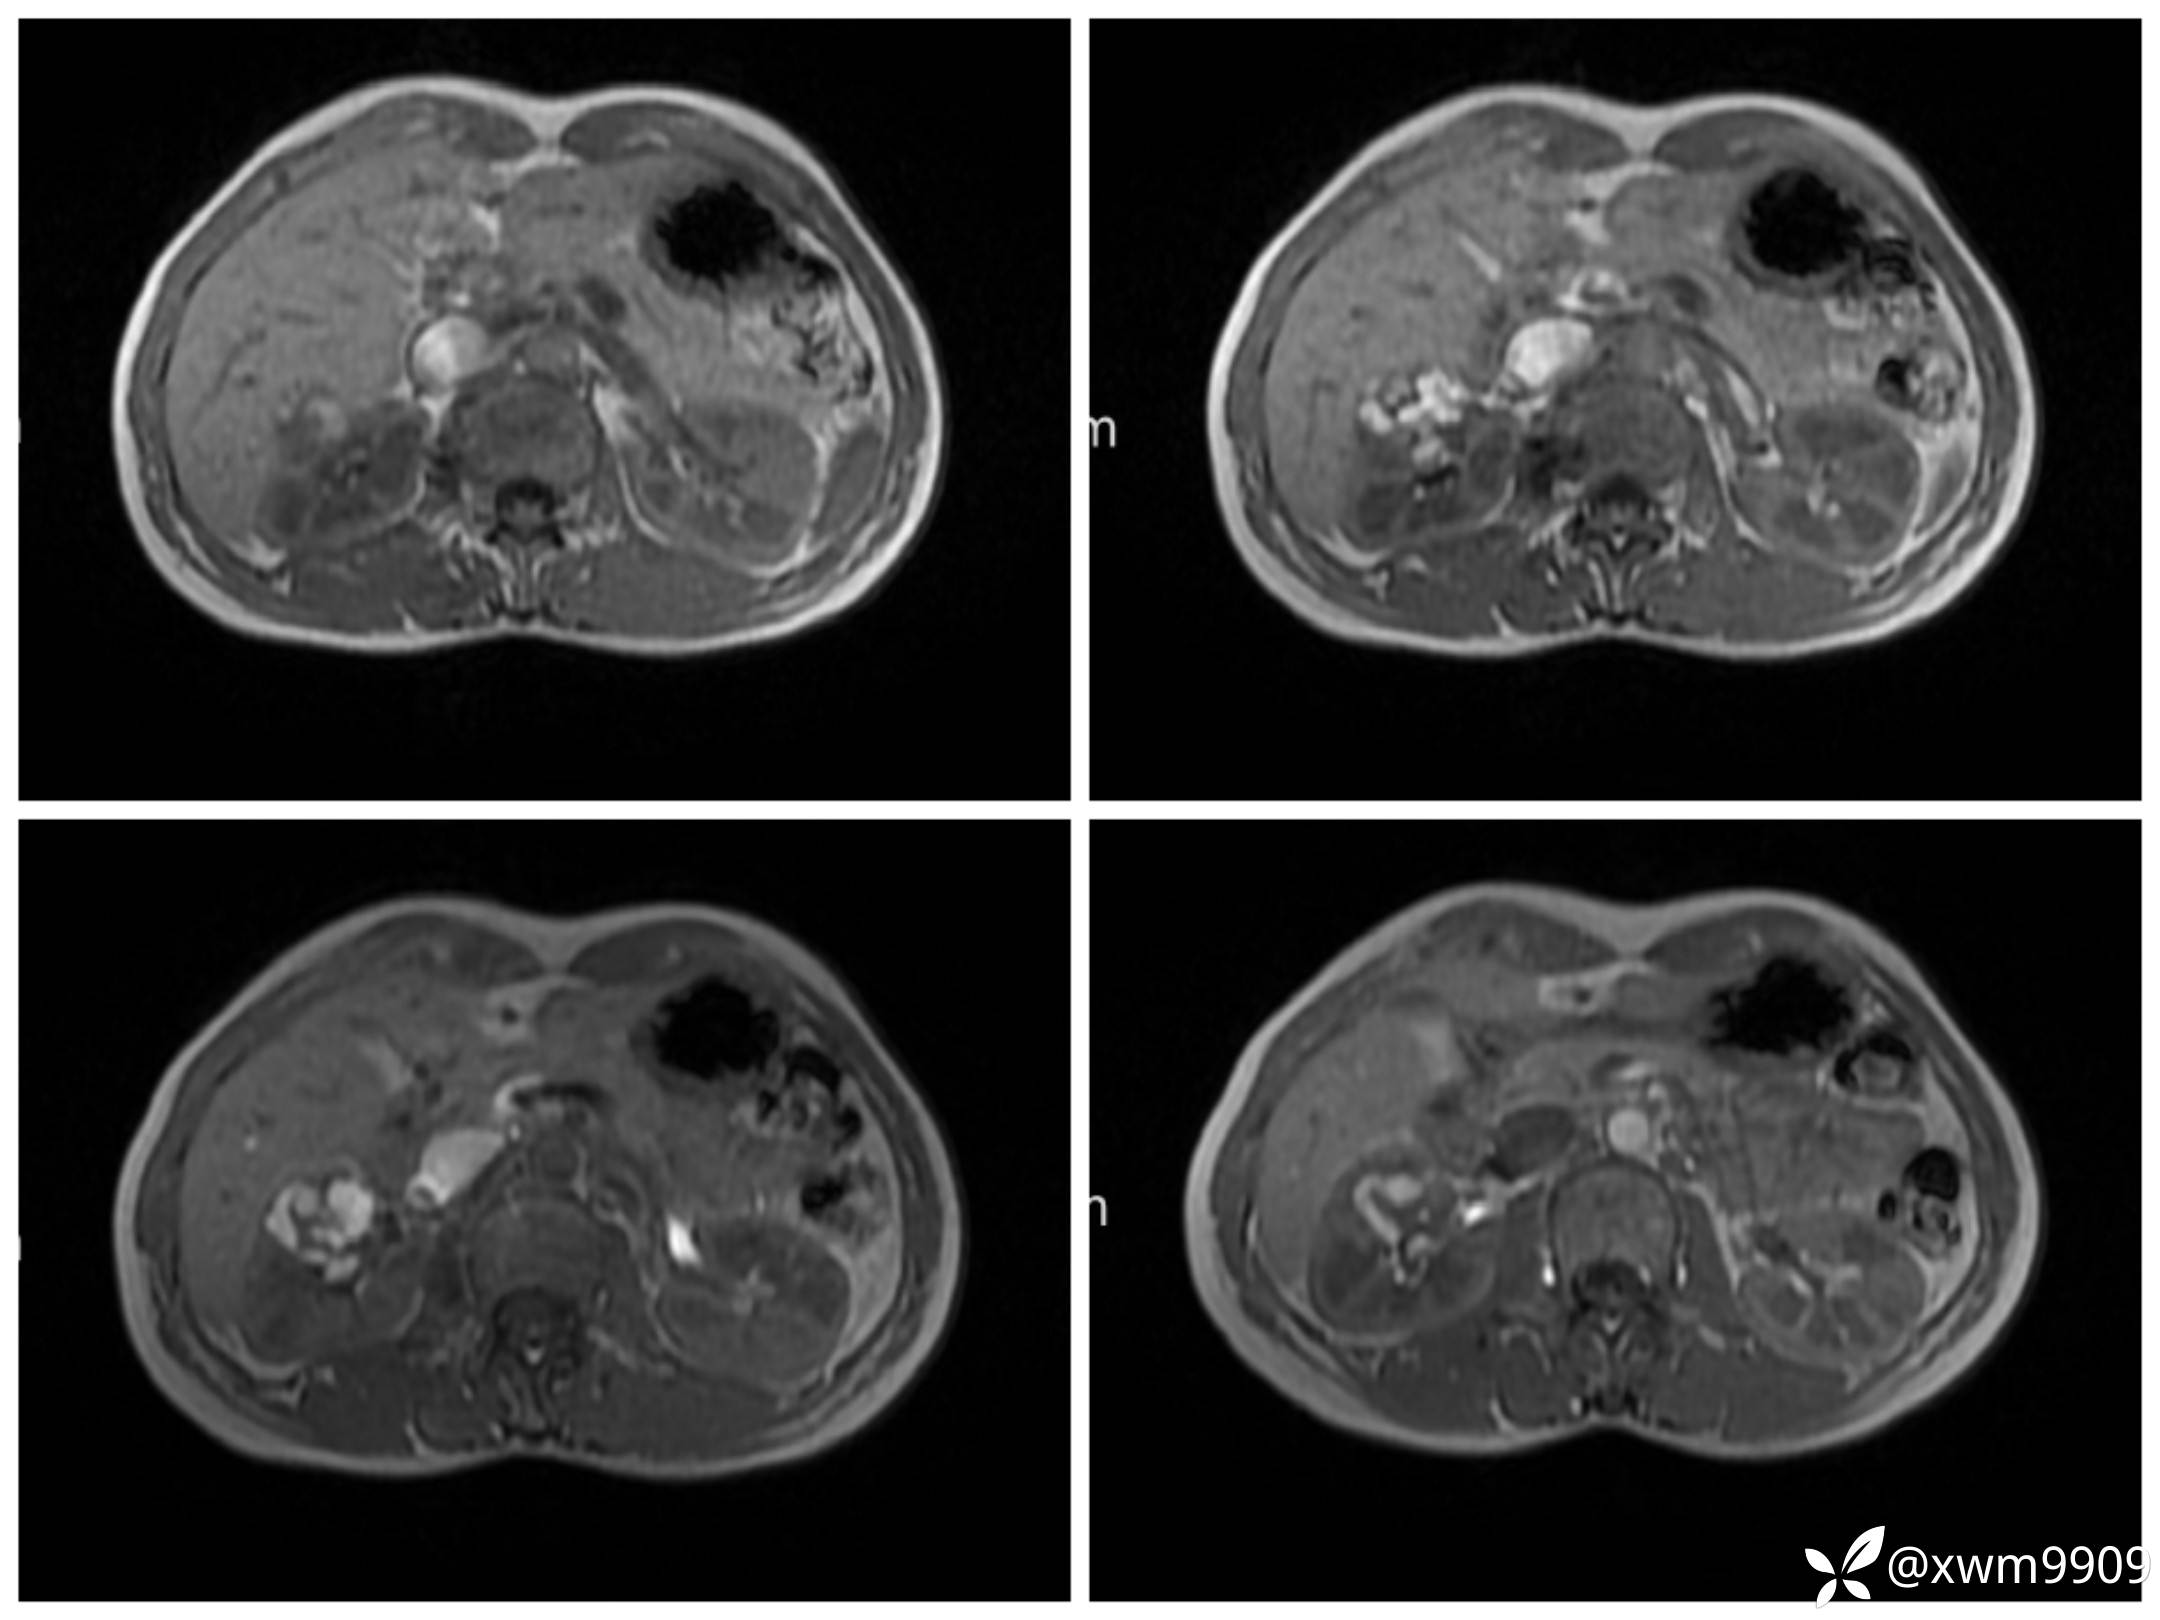

T2:

反相位:

同相位:

LAvA:

A:

v:

平衡期: